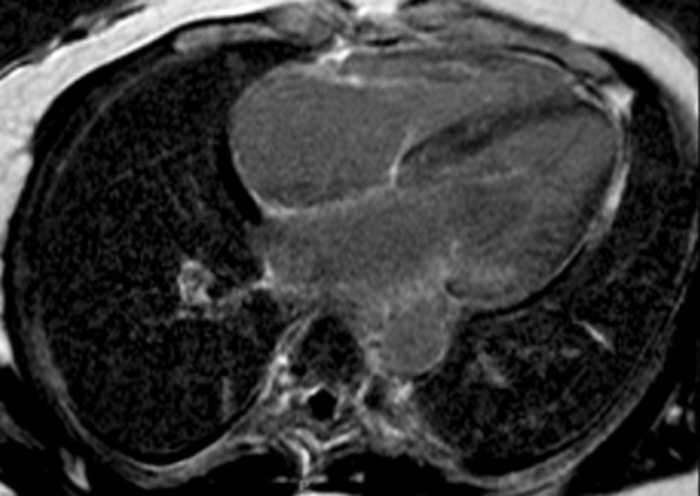

3. Cardiac MRI can be very sensitive for the detection of myocardial infiltration but does not confirm the type of CA